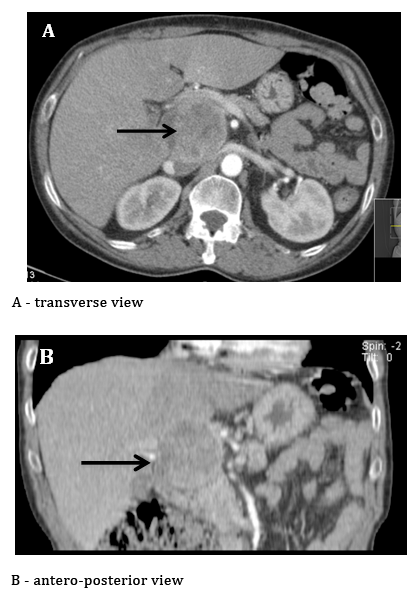

A 60year-old female with a history of Diabetes mellitus type 2, under treatment with sitagliptin and metformin and severe arterial hypertension treated with 4drugs (nebivolol, lecarnidipine, olmesartan and hydrochlorothiazide), was admitted to the Internal Medicine Department due to gastroenteritis and dehydration-associated acute renal failure (ARF). She reported weight loss (more than 15%), anorexia, asthenia, polydipsia, polyuria and frequent episodes of muscle cramps, with 1year of evolution. She presented no risk factors for chronic liver disease. She was the mother of 4, one of them with Cushing's syndrome. An abdominal ultrasound and angio-CT was performed for the investigation of renal failure. These exams revealed a non-cirrhotic liver, with a heterogeneous hepatic nodule of 63x54mm in the caudate lobe. This nodule had a heterogeneous contrast enhancement and included some areas of low density and enhancement (suggesting necrosis) (Figure 1). Liver function tests and tumor markers (CEA, CA19.9 and αFP) were assessed and unremarkable. Abnormal liver function could be present in the context of cirrhosis or obstructive jaundice and a raise in tumor markers could be interpreted in the context of primary or secondary neoplastic disease of the liver. Upper and lower GI endoscopies were performed to exclude digestive primaries, which showed no endoscopic lesions. Surgical resection was proposed due to location-related difficulties in obtaining a pre-operative biopsy.

Intraoperatively, after complete mobilization of the left hepatic lobe, the tumor was found closely attached to hepatic segment 1. It did not depend directly on the hepatic parenchyma or any other adjacent structure, such as the inferior vena cava, adrenal gland or kidney. The tumor was resected with no intraoperative incidents.